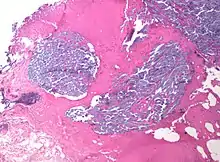

In medicine, desmoplasia is the growth of fibrous connective tissue.[1] It is also called a desmoplastic reaction to emphasize that it is secondary to an insult. Desmoplasia may occur around a neoplasm, causing dense fibrosis around the tumor,[1] or scar tissue (adhesions) within the abdomen after abdominal surgery.[1]

Desmoplasia is usually only associated with malignant neoplasms, which can evoke a fibrotic response invading healthy tissue. Invasive ductal carcinomas of the breast often have a stellate appearance caused by desmoplastic formations.

Desmoplasia refers to growth of dense connective tissue or stroma.[2] This growth is characterized by low cellularity with hyalinized or sclerotic stroma and disorganized blood vessel infiltration.[3] This growth is called a desmoplastic response and occurs as result of injury or neoplasia.[2] This response is coupled with malignancy in non-cutaneous neoplasias, and with benign or malignant tumors if associated with cutaneous pathologies.[3]

Desmoplasia is thought to have a number of underlying causes. In the reactive stroma hypothesis, tumor cells cause the proliferation of fibroblasts and subsequent secretion of collagen.[3] The newly secreted collagen is similar to that of collagen in scar formation – acting as a scaffold for infiltration of cells to the site of injury.[12] Furthermore, the cancer cells secrete matrix degrading enzymes to destroy normal tissue ECM thereby promoting growth and invasiveness of the tumor.[3] Cancer associated with a reactive stroma is typically diagnostic of poor prognosis.[3]